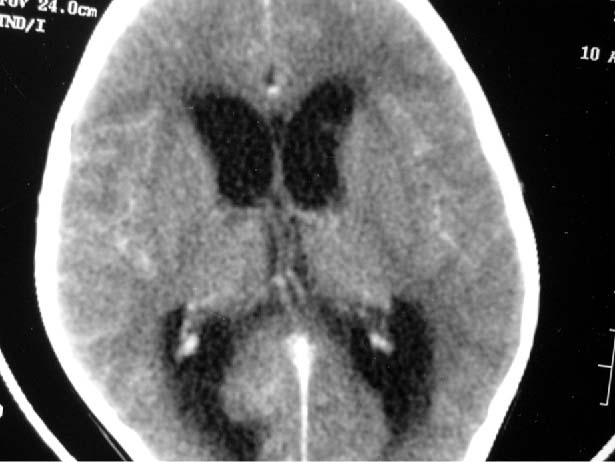

View Brain Ct Scan With Contrast Procedure UK. But soft tissues don't show up as well. While a ct scan is helpful in displaying some aspects of the head and brain, an mri scan sometimes has higher sensitivity.

A ct scan takes pictures of the inside of the body. A ct or cat scan is a shortened name for computerized tomography. Bun and creatinine must be done within 72 hours of the scan.

A ct scan takes pictures of the inside of the body. Patients with a history of allergy to. Ask questions if you don't understand. Ct of the brain with lorenz protocol.